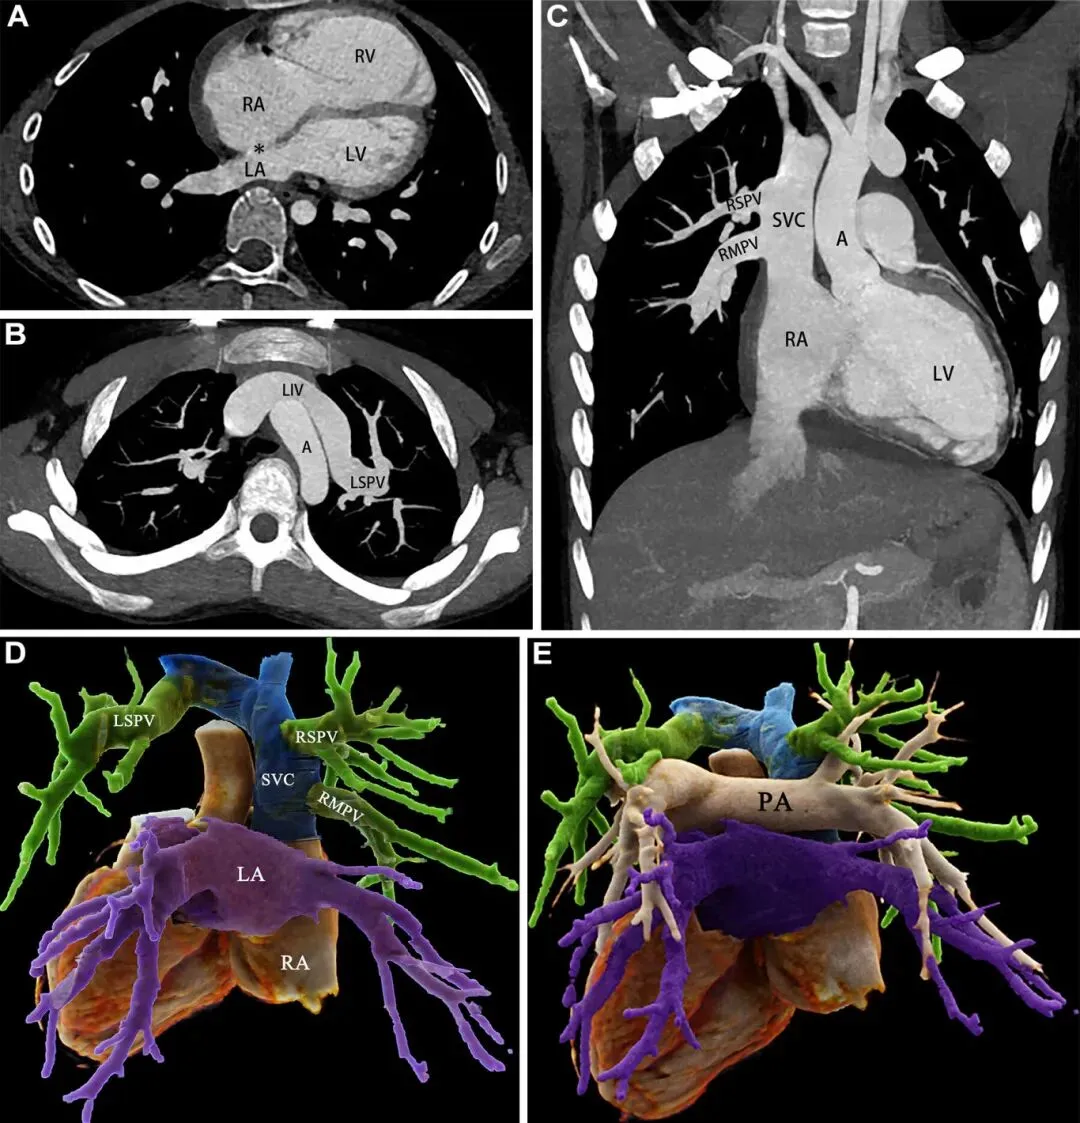

患者,13岁,女孩,双侧部分性肺静脉异位引流的影像学表现。

(A) 轴位CT血管造影图像显示明显的房间隔缺损(*)、右心房(RA)和右心室(RV)扩大,以及左心房(LA)缩小。

(B) CT血管造影轴位最大密度投影图像显示左上肺静脉(LSPV)引流至左头臂静脉,即左无名静脉(LIV)。

(C) 冠状位最大密度投影图像显示右上肺静脉(RSPV)和右中肺静脉(RMPV)引流至上腔静脉(SVC),最终血液流入右心房。

(D) 动态渲染图(后视图)展示了正常(紫色)和异常(绿色)的肺静脉回流,其中左上肺静脉、右上肺静脉和右中肺静脉经左头臂静脉和上腔静脉(蓝色)回流至右心房。

(E) 动态渲染图(后视图)清晰地描绘了肺静脉和肺动脉之间的空间关系。

A = 主动脉,LV = 左心室,PA = 肺动脉。